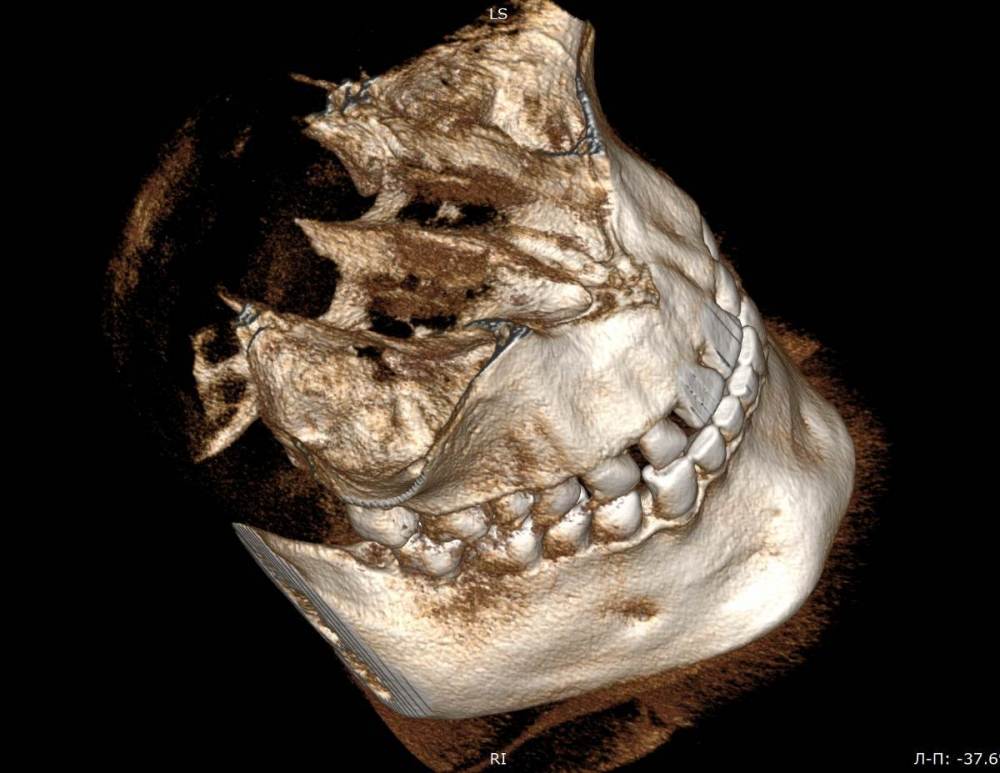

Mnrg Опубликовано 6 июля, 2023 Поделиться Опубликовано 6 июля, 2023 Всех приветствую! Беспокоит правосторонний гайморит и тонзиллит. Сделали КТ, нашли восьмерку, но предложили вместо удаления восьмерки депульпировать шестерку, консилиум сошелся во мнении, что корень перфорирует пазуху и пломба слишком близко к нерву, возможно воспаление. При зондировании между 6 и7 слегка побаливает десна, шестерка не беспокоит, холод чувствует, но не болит. Восьмерку предложили оставить. Спорить не стал, лишь решил собрать воедино мнения специалистов, т.к ближайшие более менее нормальные клиники от 100км. Архив с файлами КТ прикрепил, прошу специалистов глянуть и поделиться мнением, с чего все-таки начать, помочь разобраться.Archive.rar Ссылка на комментарий

wladdX Опубликовано 7 июля, 2023 Поделиться Опубликовано 7 июля, 2023 (изменено) Гайморит у вас совершенно необязательно имеет одонтогенную природу (вызван зубами). Судя по КТ, зуб 16 может быть виновником (а может и не быть). Для уточнения нужна также проверка витальности его пульпы (жив нерв или нет). Если пульпа нежизнеспособна, то этот зуб почти наверняка поддерживает воспалительный процесс в пазухе. Зуб 18 вряд ли нужно трогать. Лежит он себе в кости и пускай, никому он там не вредит. Да он вплотную прилежит к корням зуба 17, но и только. С внешней средой не контактирует. Никакого негативного влияния на соседние зубы он оказывать не должен: формирование корней завершено, потенции к росту и какому-либо движению нет. Удаление зуба 18 в данной ситуации вряд ли оправдано. Процедура не самая простая, но и не запредельной сложности. Изменено 7 июля, 2023 пользователем wladdX Ссылка на комментарий

Mnrg Опубликовано 7 июля, 2023 Автор Поделиться Опубликовано 7 июля, 2023 6 минут назад, wladdX сказал: Гайморит у вас совершенно необязательно имеет одонтогенную природу (вызван зубами). Судя по КТ, зуб 16 может быть виновником (а может и не быть). Для уточнения нужна также проверка витальности его пульпы (жив нерв или нет). Если пульпа нежизнеспособна, то этот зуб почти наверняка поддерживает воспалительный процесс в пазухе. Зуб 18 вряд ли нужно трогать. Лежит он себе в кости и пускай, никому он там не вредит. Да он вплотную прилежит к корням зуба 17, но и только. С внешней средой не контактирует. Никакого негативного влияния на соседние зубы он оказывать не должен: формирование корней завершено, потенции к росту и какому-либо движению нет. Удаление зуба 18 в данной ситуации вряд ли оправдано. Процедура не самая простая, но и не запредельной сложности. Шестерку проверяли холодом - чувствует, не знаю, означает ли это жизнеспособность пульпы, но на холод реагировал немного сильней других зубов. Сегодня открыл КТ программой RadiAntViewer и обнаружил в 3D просмотре визуальные признаки нахождения части восьмерки в краю пазухи. Конечно я не могу утверждать, т.к не врач и насколько понимаю это режим моделирования, но все же выглядит убедительно на мой скромный взгляд. Еще один глупый вопрос, если позволите) Возможно ли в шестерке в одном из трех корней воспаление и нерв разрушен, а другие два при этом будут создавать чувствительность, т.е быть "живыми" или же это фантастика? Деньги запросили немалые для нашего региона за депульпацию (13к) поэтому пытаюсь собрать как можно больше информации прежде, чем принимать решения. Ссылка на комментарий